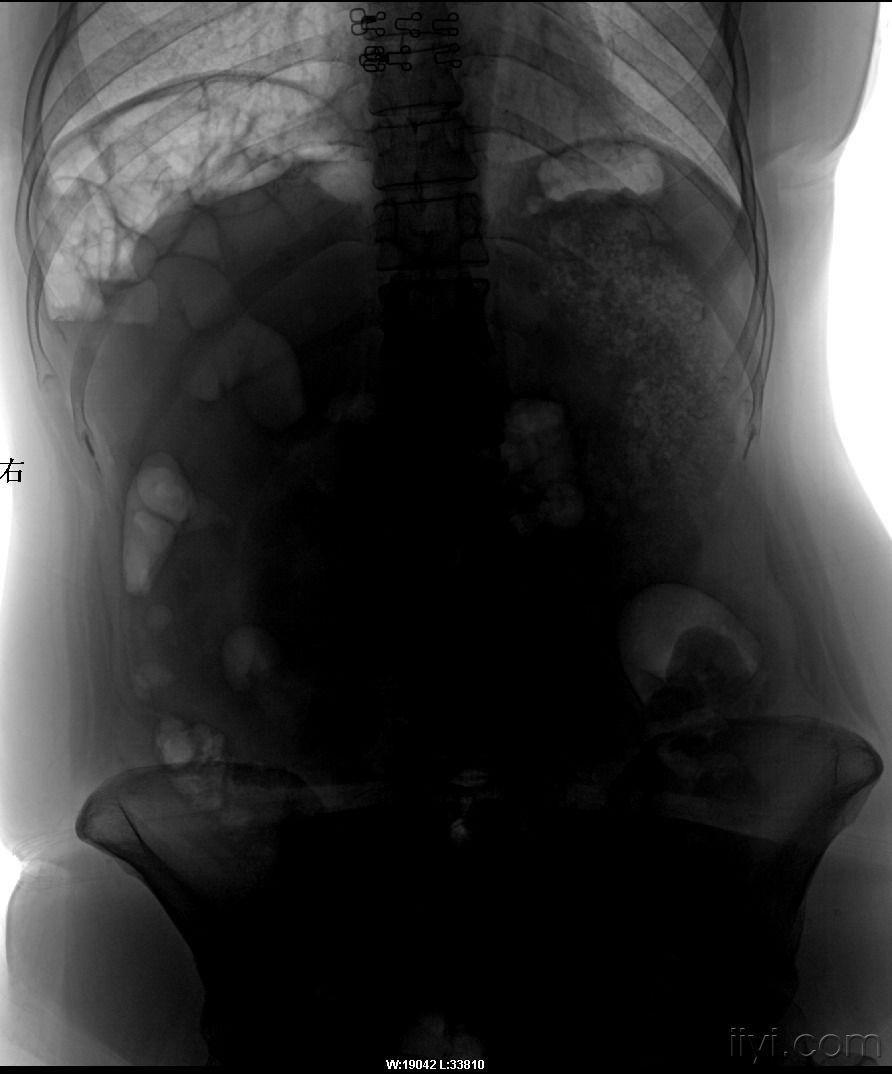

胃穿孔立位腹平片图片,胃穿孔图片的图片

胃肠道穿孔表现有气腹,腹腔积液,腹脂线异常和麻痹性肠胀气,其中以

上消化道穿孔?(立位腹部平片)